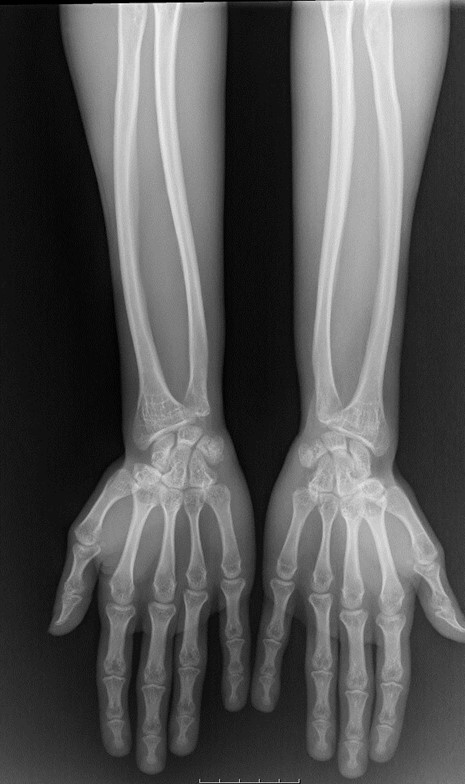

AP x-ray of the forearms shows bowing of the radius and ulna, as well as thinning of the diaphysis and widening of the metaphysis (Figure 3).

Figure 3: AP x-ray of the forearms shows thinning of the diaphysis and widening of the metaphysis of the ulna and radius with decreased density of these bones.

Also showing the bowing of the forearm bones.